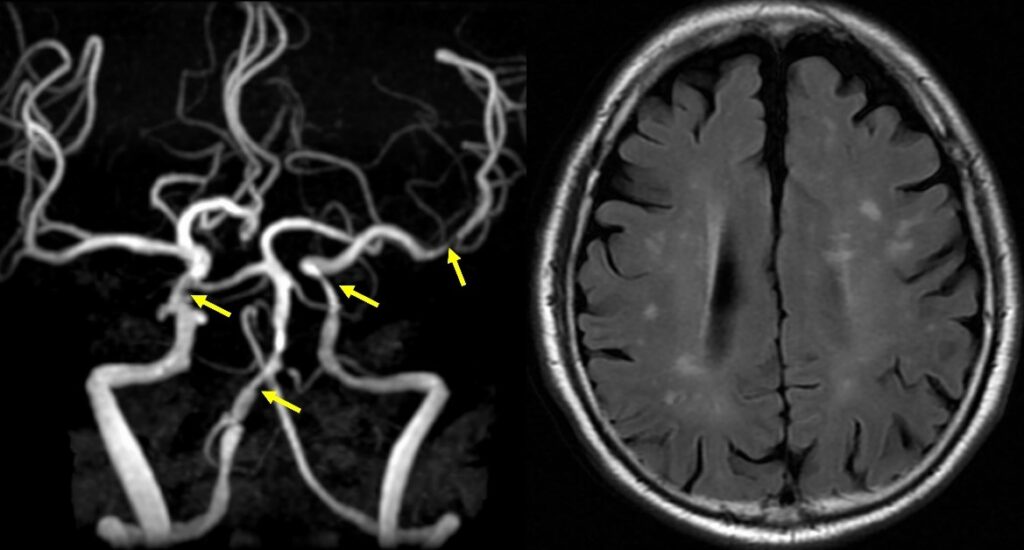

図の説明;左:脳MRAで脳血管に多発性の動脈硬化性狭窄を認める(矢印)。右:MRIでは、脳の老化現象である血管性の異常信号(白い斑点)が見られる。現在無症状で血液サラサラの薬を内服して経過観察中。

太い血管の閉塞による脳梗塞が起こった場合は、発症6時間以内であれば血管の中から血栓を取り除く治療を行うことにより、症状が改善する可能性があります。アテローム性梗塞やラクナ梗塞を予防するには、脳ドックなどで、頸動脈エコーや脳MRI/MRAを定期的に行い、脳や首の動脈の動脈硬化やそれによる血管狭窄の有無をチェックし、必要に応じて血液をさらさらにする薬を内服して、血栓ができるのを予防することが重要です。

狭窄の程度がひどい場合や、軽度脳梗塞や一過性の脳症状を呈する場合は、狭窄部にステントを置いたり、脳血流を増やす手術が必要になったりする場合もあります。また、動脈硬化は、糖尿病、高血圧、高脂血症などがあると悪化する傾向があり、認知症の原因ともなるので、これらの生活習慣病の予防と治療も重要です。